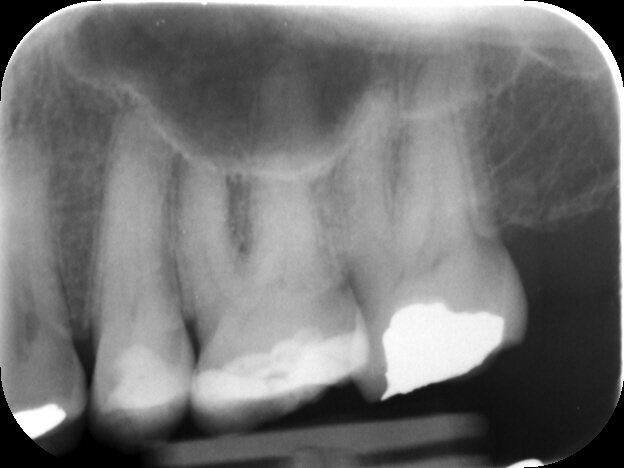

UL7 with recently placed occlusal restoration, pulp calcifications can be seen